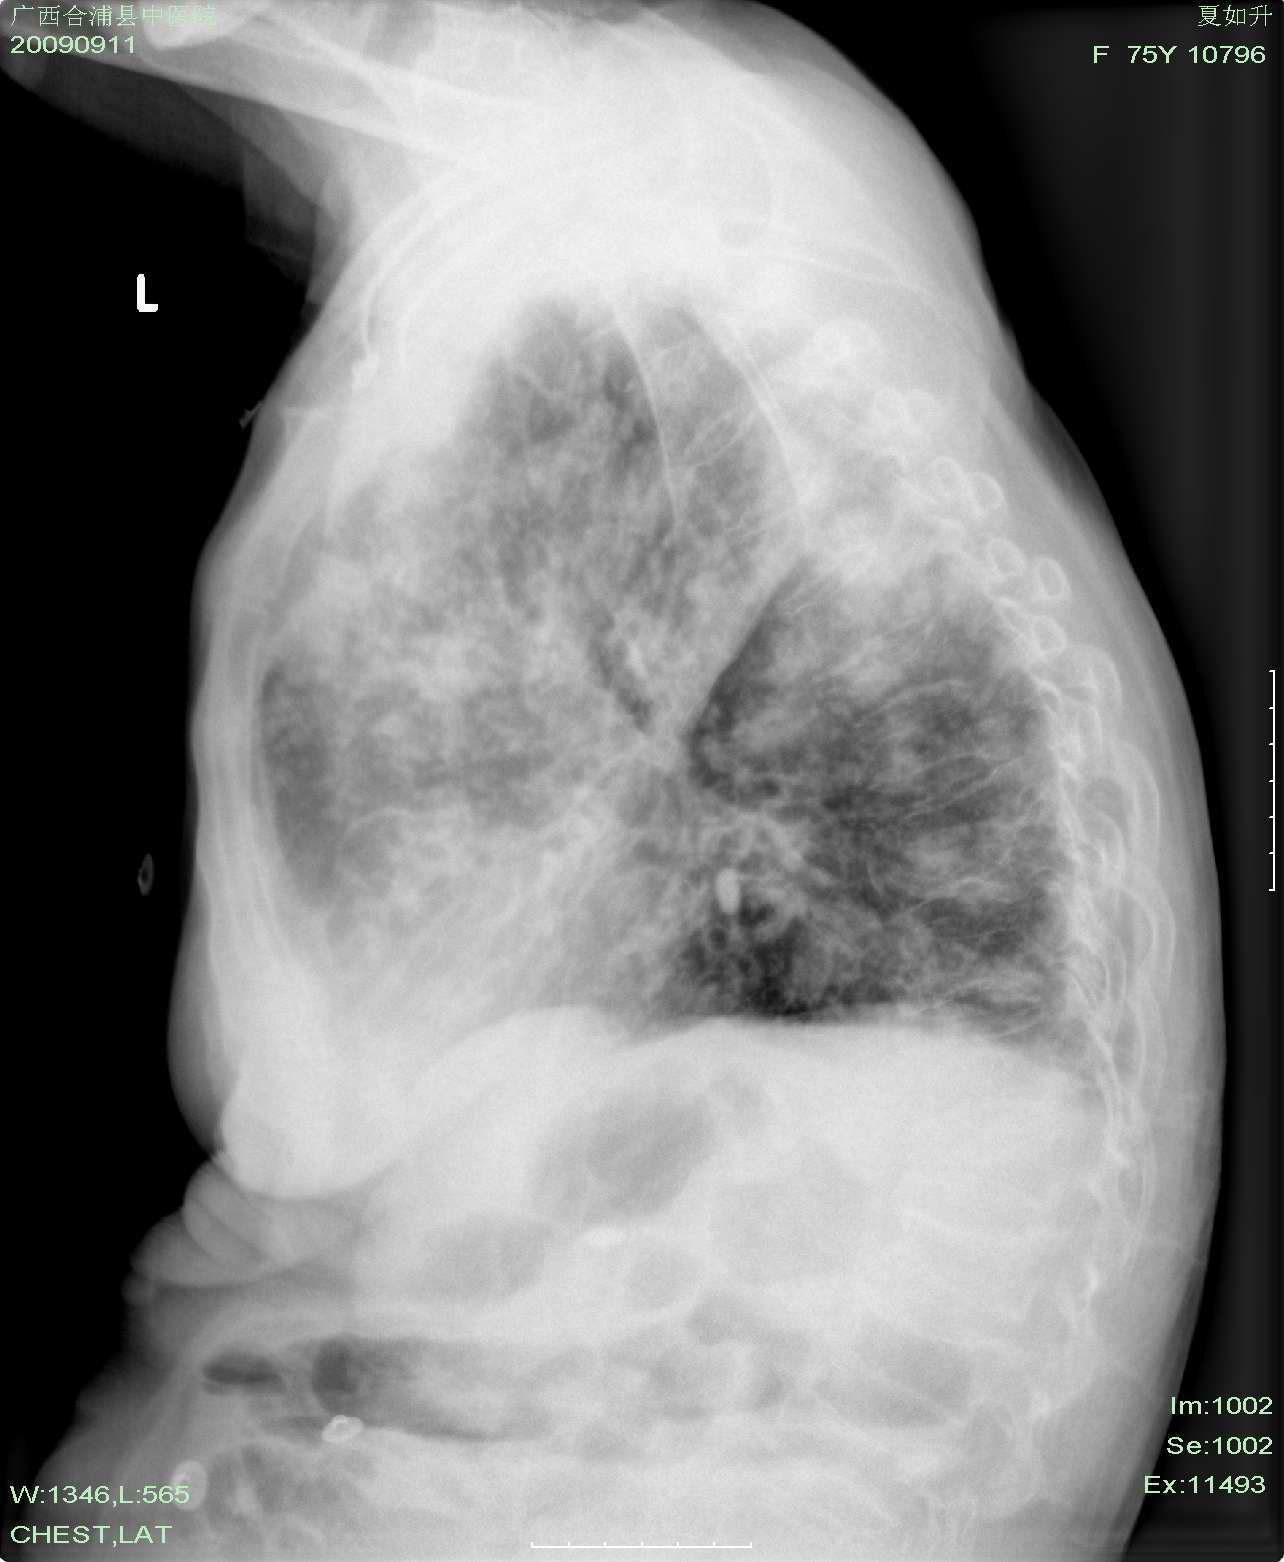

以下是引用hhx58在2009-9-11 19:48:00的发言:[br]有4个是心电监护的电极。[br]ct图片可见有肺气囊。但未拿到片上传。

以下是引用dyqct在2009-9-12 8:42:00的发言:[br]慢性支气管炎合并间质纤维化、肺气肿、支气管扩张、感染。建议ct进一步检查。

以下是引用黑白光影在2009-9-12 16:43:00的发言:[br]慢支并感染(霉菌?)